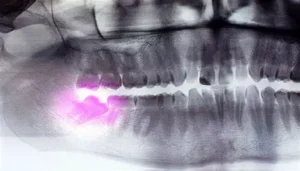

Wisdom teeth, also known as third molars, are the last set of teeth at the back of the mouth that typically appear in early adulthood,